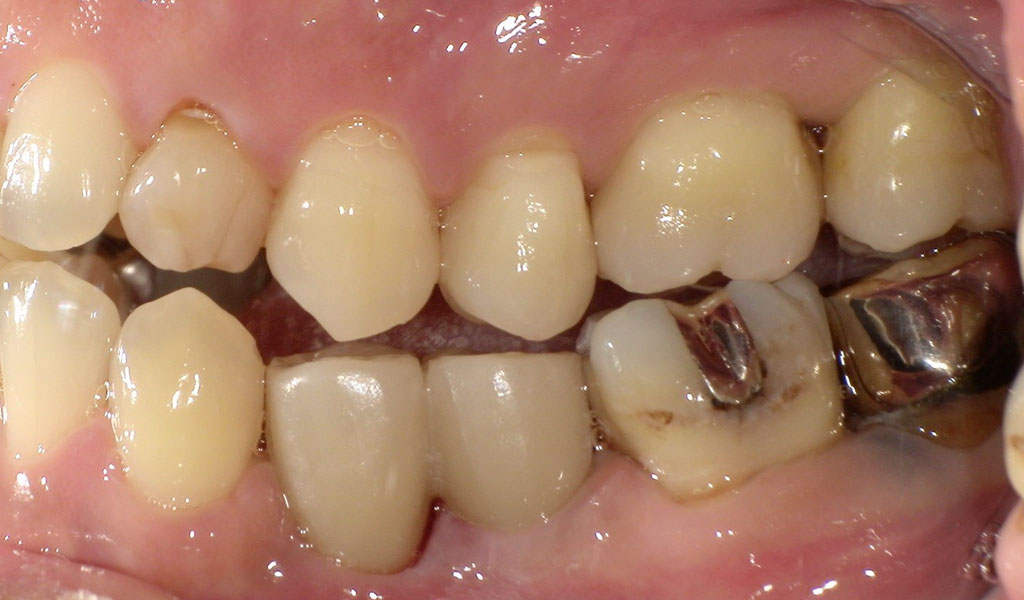

After2

左下4番の歯根が残っていたため、抜歯。通常手術にて、左下4,5番の骨にインプラントを埋め込みました。

歯周内科治療終了後、再PCR検査によりPg菌、Td菌、Tf菌の数値が問題ないレベルまで下がったことを確認。

インプラントと骨がしっかり結合するまで術後3ヶ月待ち、インプラントの上に人工の歯を被せる治療を行いました。